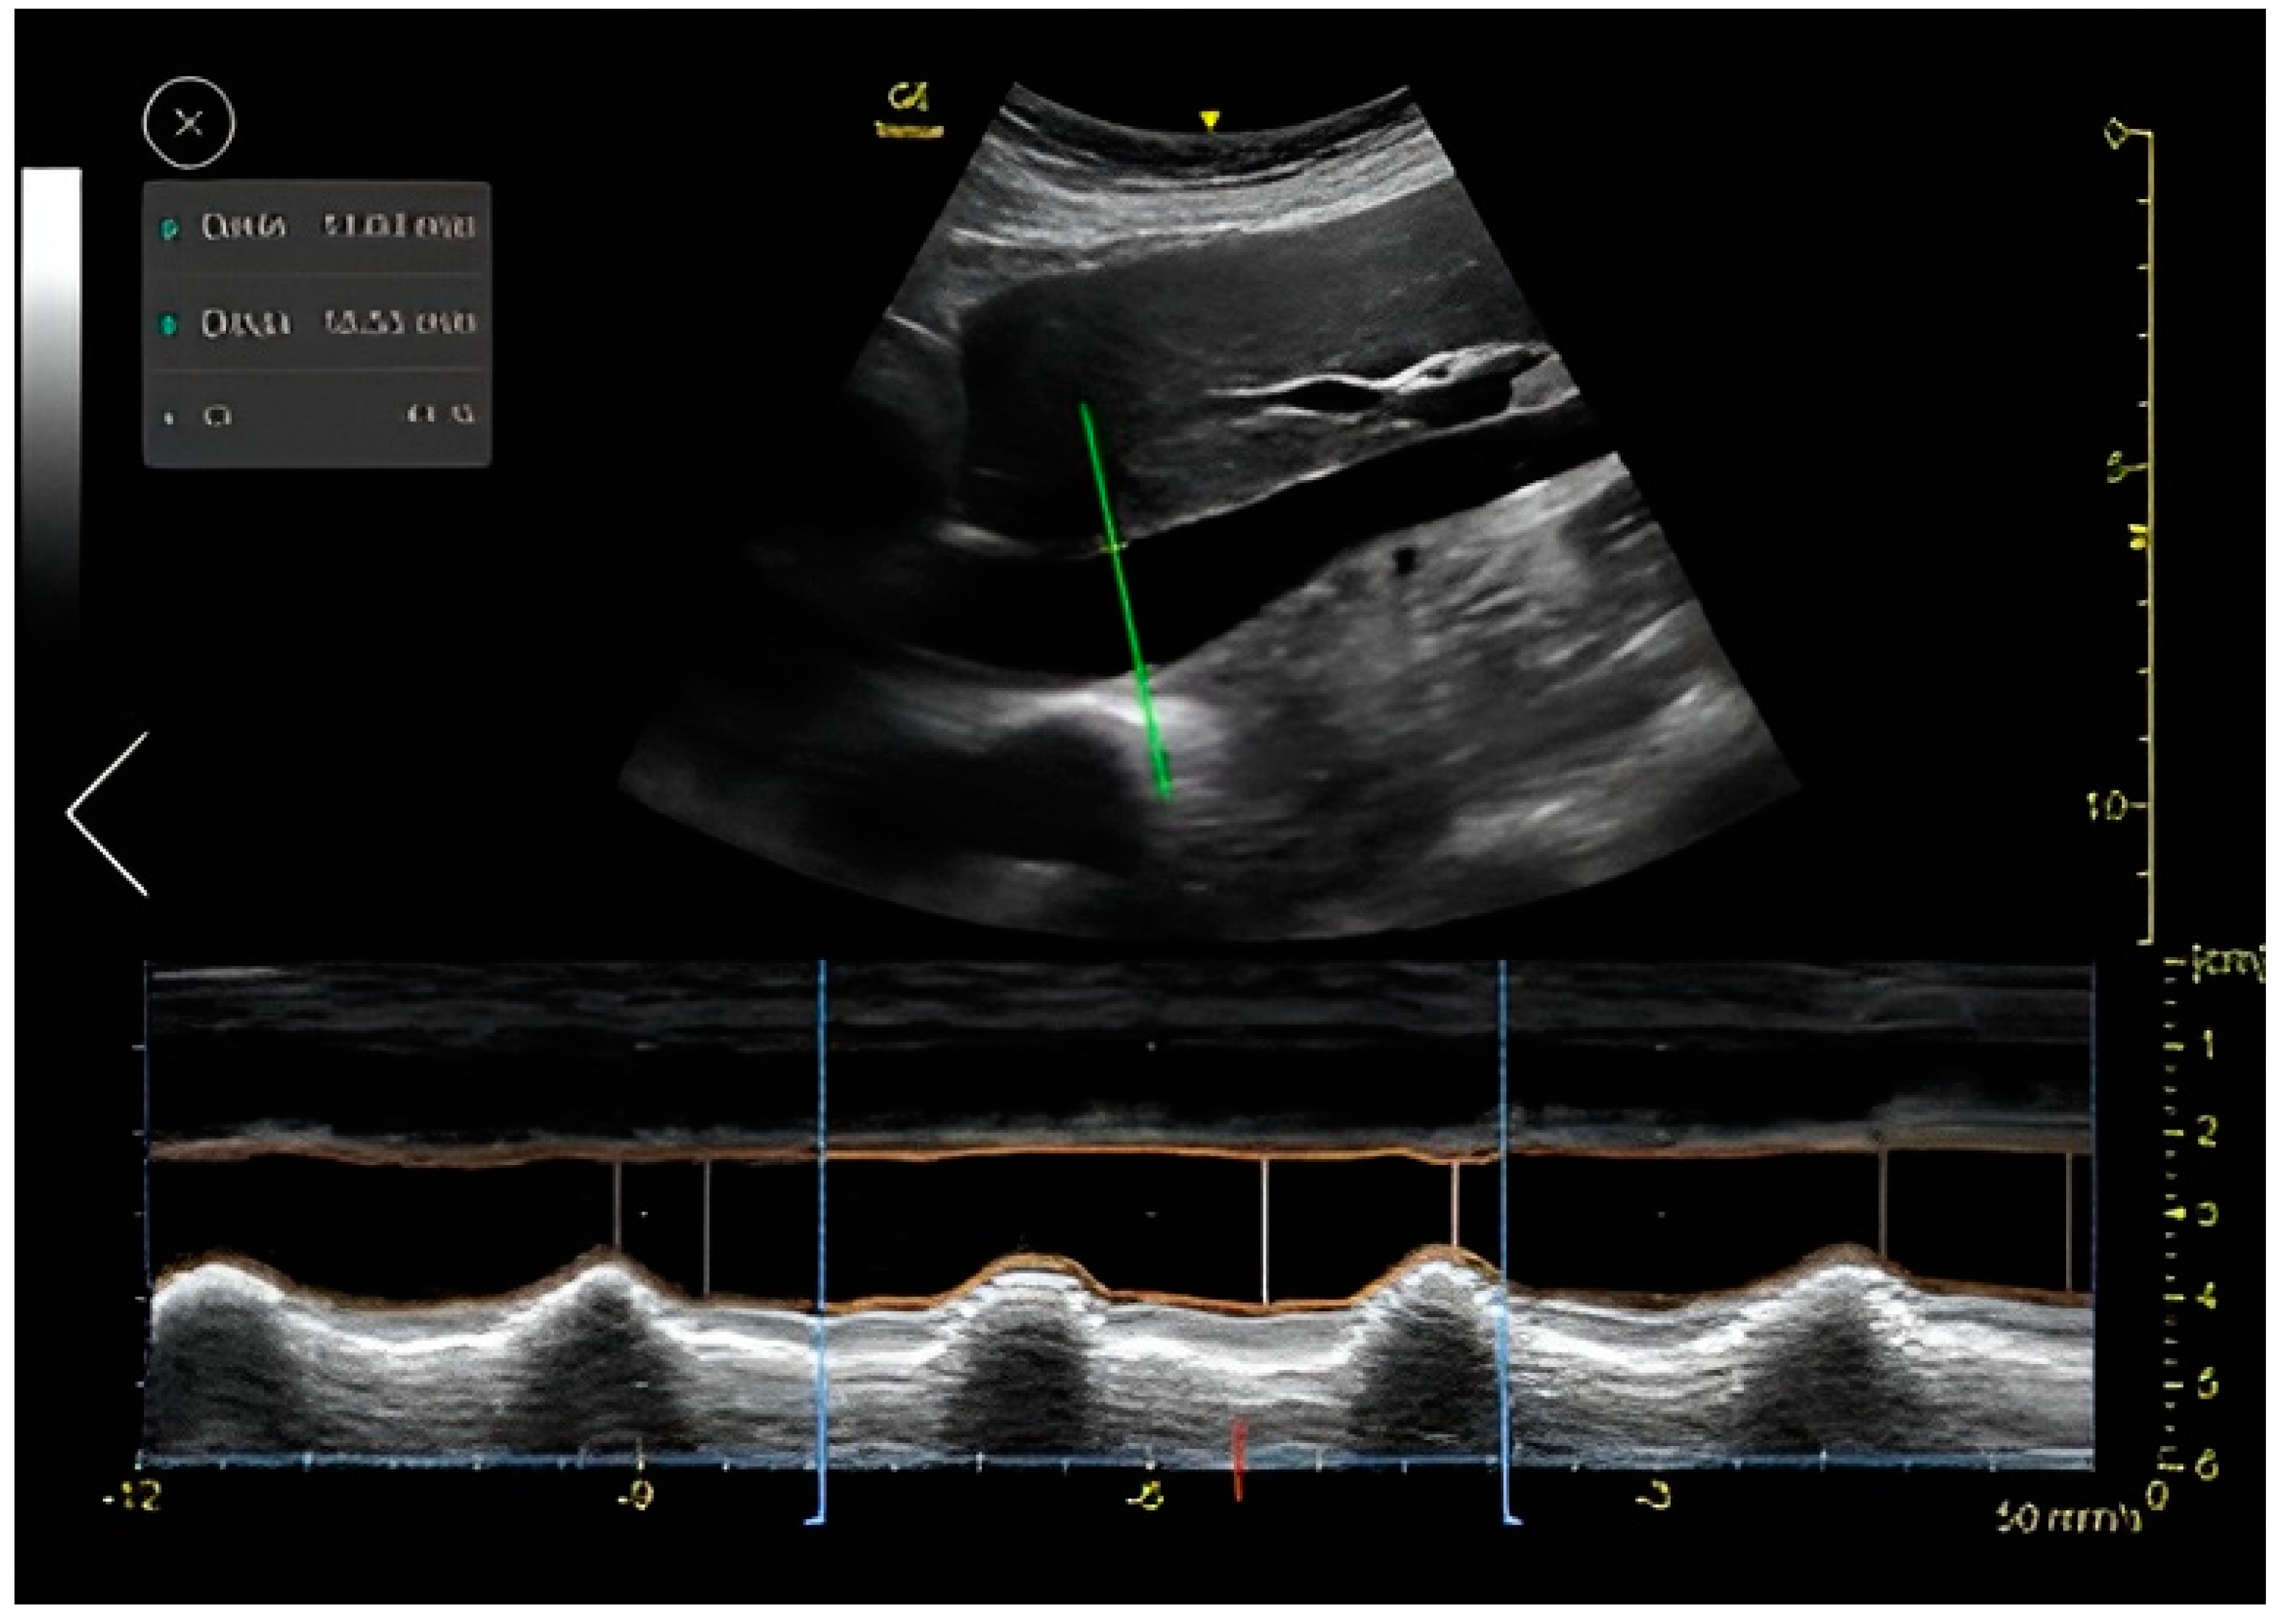

IVC CI Automatic Measuring Tool

The auto IVC tool automatically places the M-mode cursor 2–3 cm below the diaphragm. The algorithm then measures the maximum and minimum diameters of the IVC throughout a respiratory cycle (Figure 4). The auto IVC tool measures the maximum and minimum diameters of the IVC throughout the respiratory cycles in real time. The collapsibility index represents the collapsibility (diameter change) of the inferior vena cava between expiration and inspiration. The quality indicator is represented by the color of the M-mode cursor, and varies between green/yellow/red to represent excellent/average/unacceptable image quality, respectively.

Figure 4.

Auto IVC tool: auto marker placing, M-mode and data display.

For IVC size and collapsibility index assessment, the tool was found to be very reliable with an agreement coefficient of 0.536 (95% CI, p = 0.009) when utilized on good IVC image quality and unreliable when utilized on medium and low image quality (Table 3). This is probably due to the technical challenge of measuring the diameter of the IVC when the vein borders are not clearly demonstrated and when there is variability in the placement of the M-mode cursor (Figure 4). We confirm that when the image quality of the IVC is good, this tool is reliable, and the automatic assessment of the IVC CI can be used.